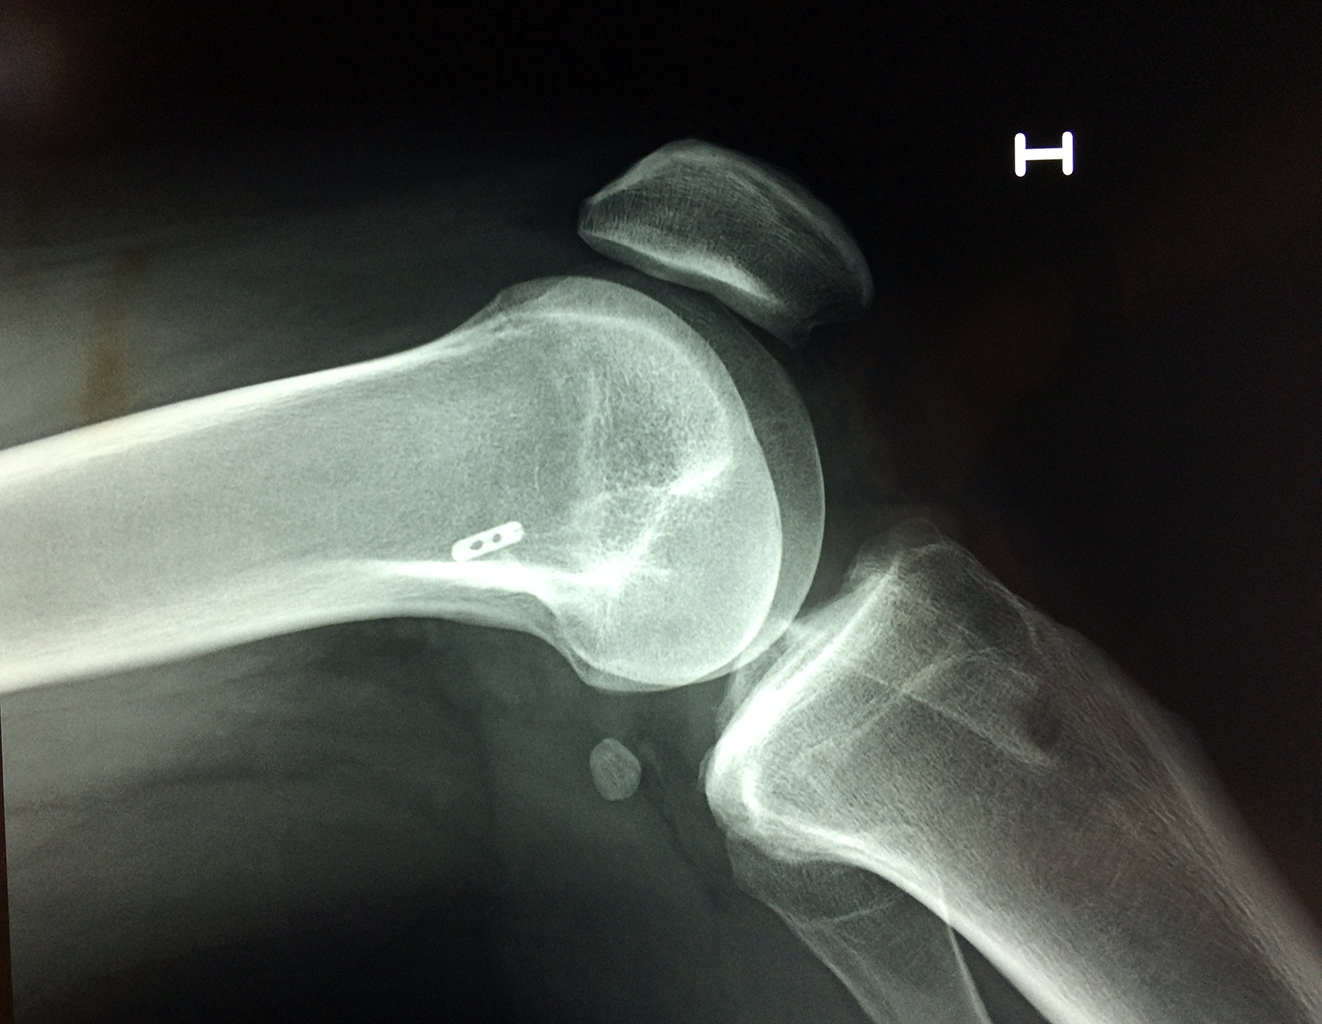

Cirugía de Fémur - Rodilla

La artroscopia de rodilla es un cirugía en el cual la estructura interna de la articulación es examinada ya sea para realizar un diagnostico o para realizar un tratamiento, este procedimiento se realiza utilizando un instrumento parecido a un pequeño tubo llamado artroscopio.